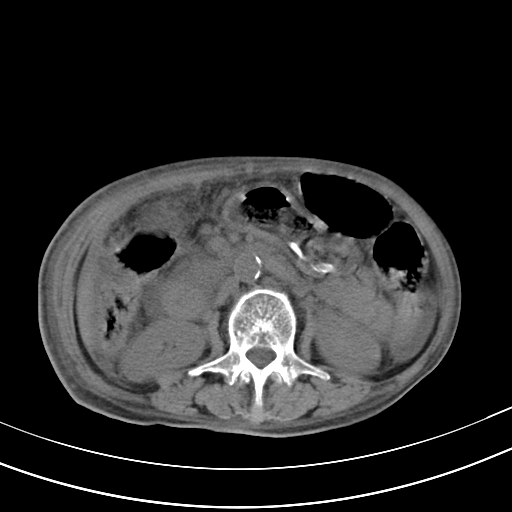

病人上腹部胀痛拌全身黄染八天

结石好象不明显吧?胆管稍扩张。

右侧少量胸水,胆囊增大,肝内胆管扩张,肝门部结构杂乱,建议增强。

肝内胆管及胰管扩张考虑为胰头区占位,肝门淋巴结增多,肝内多发低密度影,考虑为转移。门脉高压,脾大,胆囊大。

肝内胆管及胰管扩张,胰头增大考虑为胰头区占位,肝门淋巴结增多,考虑为转移。建议增强,脾大,胆囊大,壁厚,慢性胆囊炎。胃壁好像也增厚,且有一肿物。

1)考虑胰头癌并胆系低位梗阻;建议行ct增强扫描检查。2)慢性胆囊炎。3)脾大。4)少量腹水。5)双侧少量胸腔积液。